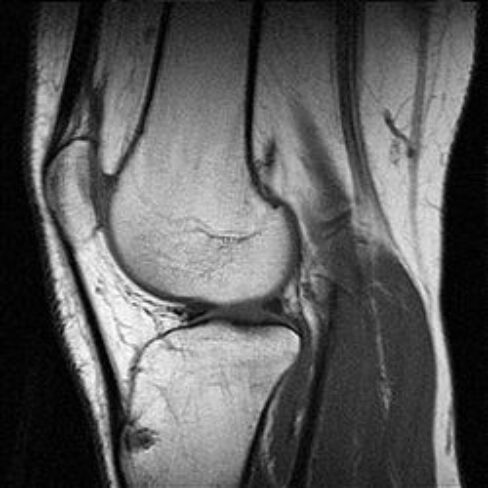

Czasem masz problemy z oceną stawów?

A może na co dzień zajmujesz się układem mięśniowo-szkieletowym?